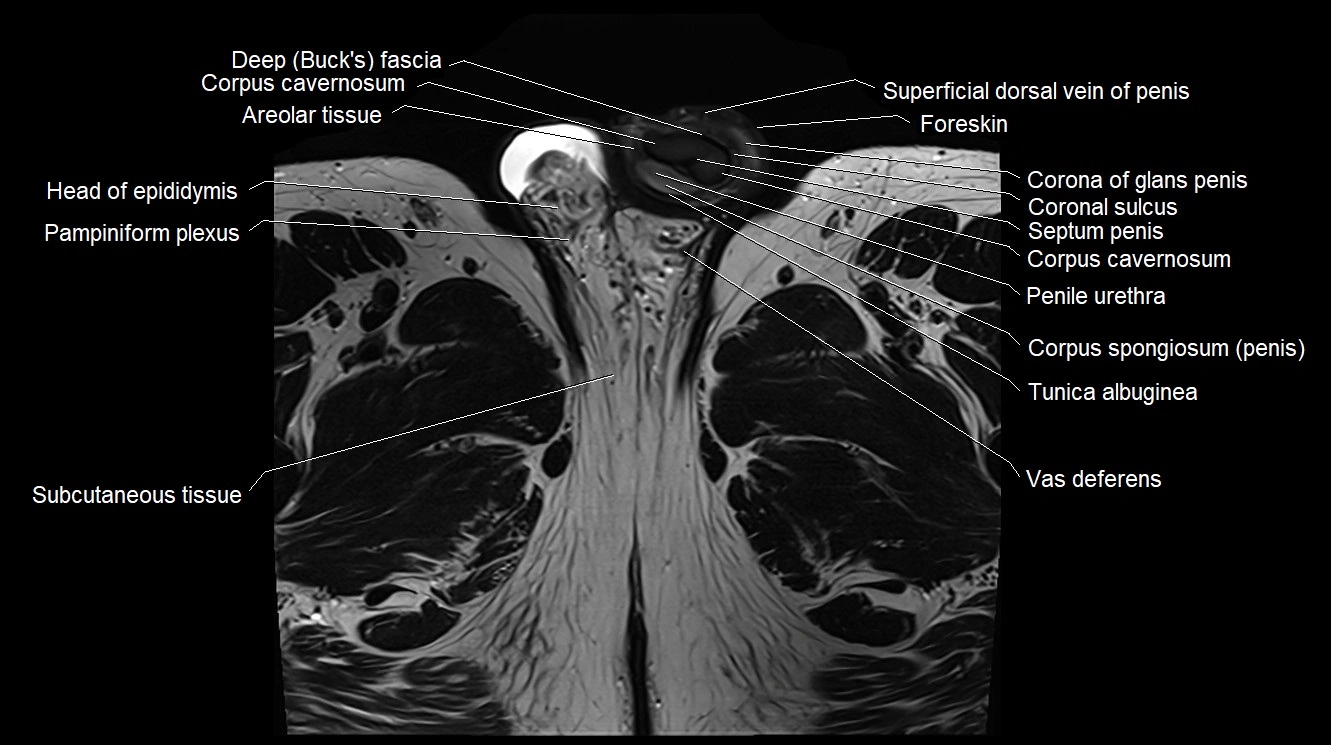

MRI image